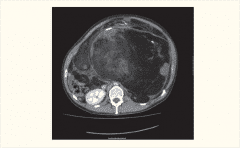

腹膜后恶性肿瘤(retroperitoneal tumors)是指来自腹膜后间隙的脂肪、疏松结缔组织、肌肉、筋膜、血管、神经、淋巴组织等发生的恶性肿瘤,并不包括原在腹膜后间隙的各个器官的肿瘤。腹膜后恶

什么是腹膜后恶性肿瘤 腹膜后脂肪肉瘤(RLS)是一种较为常见的原发性腹膜后恶性肿瘤。由于肿瘤位置较深且早期没有特异性特征,因此早期诊断很困难,很多患者确诊时已经发展到了中晚期,